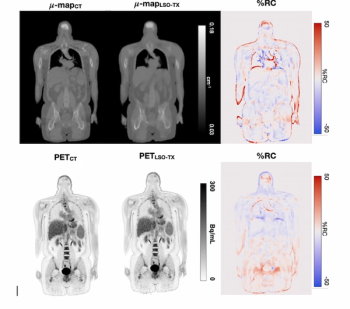

Ultra-low dosing with long axial field-of-view positron emission tomography (PET) scanners facilitates qualitative PET imaging at a more than 50 percent reduction of conventional radiation dosing with PET, according to new research presented at the SNMMI 2024 conference.